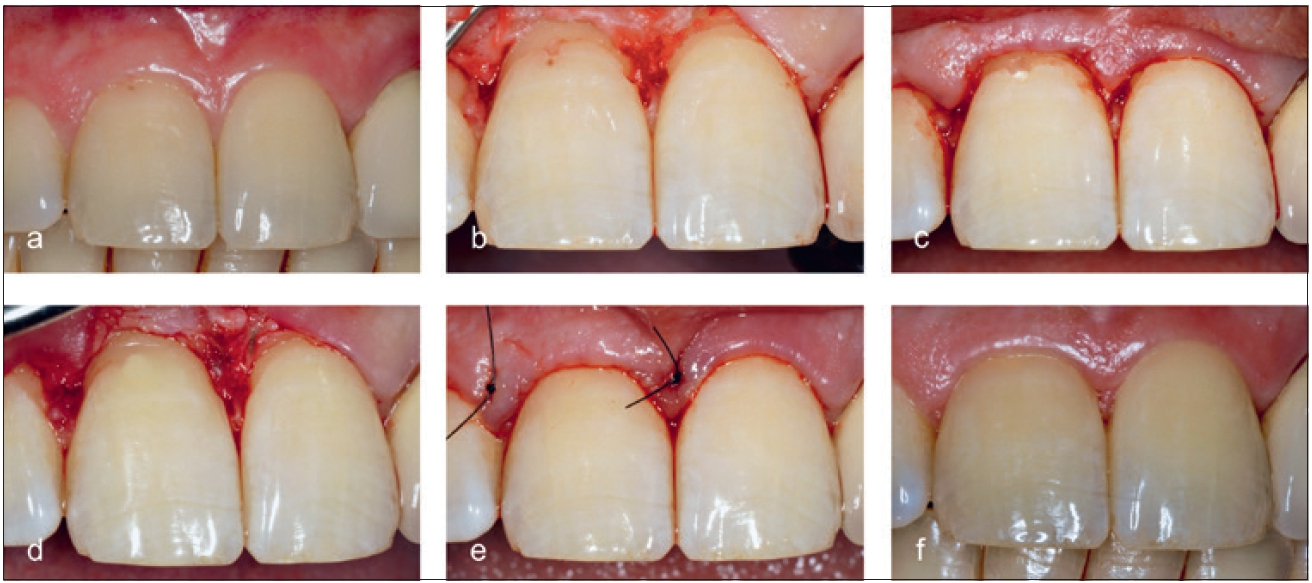

Liegt der Defekt weitgehend supraosseär und ist ein ungehinderter Zugang möglich, kann der meist weichgewebige Inhalt von außen entfernt werden (Abb. 14). Falls das Resorptionsgewebe nicht vollständig erreichbar ist, können 90%ige Trichloressigsäure (TCA) oder 3- bis 5%iges Natriumhypochlorit (NaOCl) angewendet werden, um eine Blutstillung zu erreichen und das Restgewebe aufzulösen [21,32] (Abb. 15).

Dr. Widbiller

Die Restauration der zervikalen Kavität erfolgt in Bereichen, die der Mundhöhle zugängig sind, mit Kompositen in Adhäsivtechnik (Abb. 14 und 15). Liegt der Defekt in unmittelbarer Nähe zur vitalen Zahnpulpa oder wurde das Pulpakavum eröffnet, sollten vitalerhaltende Maßnahmen im Sinne einer indirekten bzw. direkten Überkappung vorgenommen werden. Bereiche, die direkt an Knochen grenzen, müssen mit hydraulischen Kalziumsilikatzementen versorgt werden. Hierzu eignen sich Mineraltrioxidaggregat (z.B. ProRoot MTA, Dentsply DeTrey GmbH, Konstanz) oder modifizierte bioaktive Zemente (z.B. Biodentine, Septodont GmbH, Niederkassel). Diese härten in Anwesenheit von Feuchtigkeit aus und bieten biologisch günstige Eigenschaften, sodass knöcherne Defekte ausheilen können.